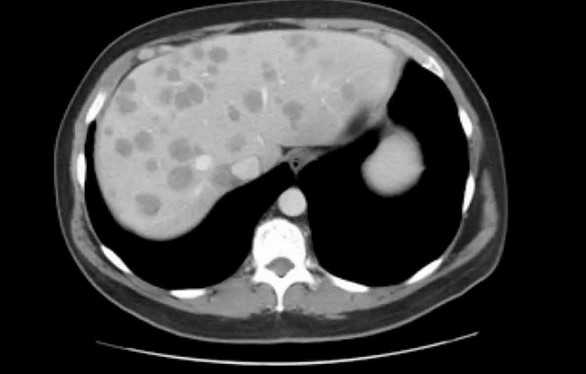

Метастазы в печени на снимке МСКТ